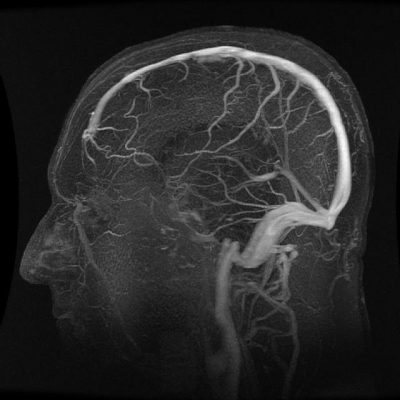

Vengono effettuate biopsie stereotassiche cerebrali con l’utilizzo di un casco stereotassico e i dati raccolti sono elaborati da sofisticati programmi di calcolo delle coordinate. Tale procedura consente la diagnosi istologica delle lesioni espansive intracraniche e offre un grado di precisione molto elevato (dell´ordine del millimetro), grazie anche all’esperienza maturata dall’équipe. L’elevata specializzazione dell’équipe ha portato all’attivazione di specifici percorsi di diagnosi e di cura, anche in situazioni di emergenza, per la patologia vascolare intra ed extracranica; i medici, in particolare, sono in grado di intervenire su aneurismi, malformazioni artero-venose, angiomi cavernosi, stenosi carotidee e vertebrali, grazie all’alta professionalità, all’utilizzo di tecniche innovative e alla collaborazione con il team di neuroradiologi.

Gli esami neuroradiologici sono eseguiti con risonanza magnetica, spettroscopia, trattografia e risonanza funzionale per definizione del volume tumorale pre e post-operatorio e valutazione della risposta alle terapie (radio e chemioterapia), in collaborazione con i medici della Neuroradiologia. La strumentazione endoscopica è di ultima generazione, con ottiche dedicate alla chirurgia ipofisaria, telecamera a 3 CCD (sensori ottici), sistema integrato di visualizzazione di immagini e registrazione (Brain Suite).

- Aneurismi, malformazioni artero-venose, angiomi cavernosi, stenosi carotidee e vertebrali (patologia vascolare intra ed extracranica)